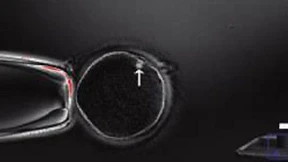

Die Blutzellen einer Maus werden zu Embryozellen. Und zwar nicht durch Gentechnik, sondern in einem Säurebad. Stammzellen, die potentiell Organe ersetzen könnten. Wieder eine Revolution in der Biomedizin?